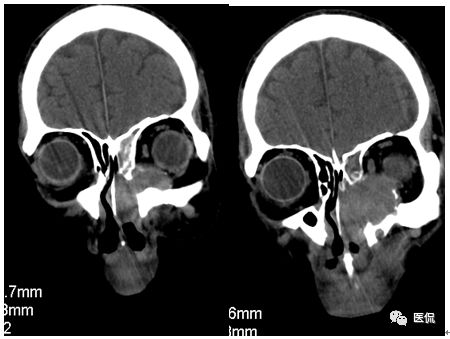

冠状位平扫

增强动脉期

CT平扫及增强示:左侧上颌窦及鼻腔可见软组织密度影,呈膨胀性生长,周围骨质压迫性吸收破坏,累及左眶,病灶密度不均匀,周边区可见点状钙化,增动脉期轻度强化,局部见小灶性稍高密度区,静脉期病灶内见不均匀明显强化,CT值最高达117HU,延迟期强化范围有所增大。

影像学表现呈软组织密度,多不均匀,表现为高低混杂密度,病变窦腔内息肉、血肿、坏死、感染共存,是病灶密度不均匀的主要原因,息肉反复出血、血管机化亦为其成因之一。病灶内钙化,可为团块状或小片状,可能为病变组织坏死后钙质沉着所致。由于病变组织内有大量炎性细胞浸润和丰富的毛细血管,增强后常有强化。有文献报道病灶增强中心区强化不明显,外周呈轻度强化,推测病灶内虽然血管丰富,但中心区容易出现血流动力学障碍,血管内常有血栓形成,中心区易发生出血坏死,另外,可能与增强扫描延迟时间选择不当有关。

本例病灶较大,周围骨质可见吸收破坏,并累及眼眶,病灶内少量钙化,增强扫描具有一定特征性,表现为动脉期轻度强化,局部见小灶性稍高密度区,静脉期病灶局部呈明显强化,CT值最高达117HU,延迟期强化范围有所增大,呈延迟渐进性强化的特点,推测为病灶内出血所致。